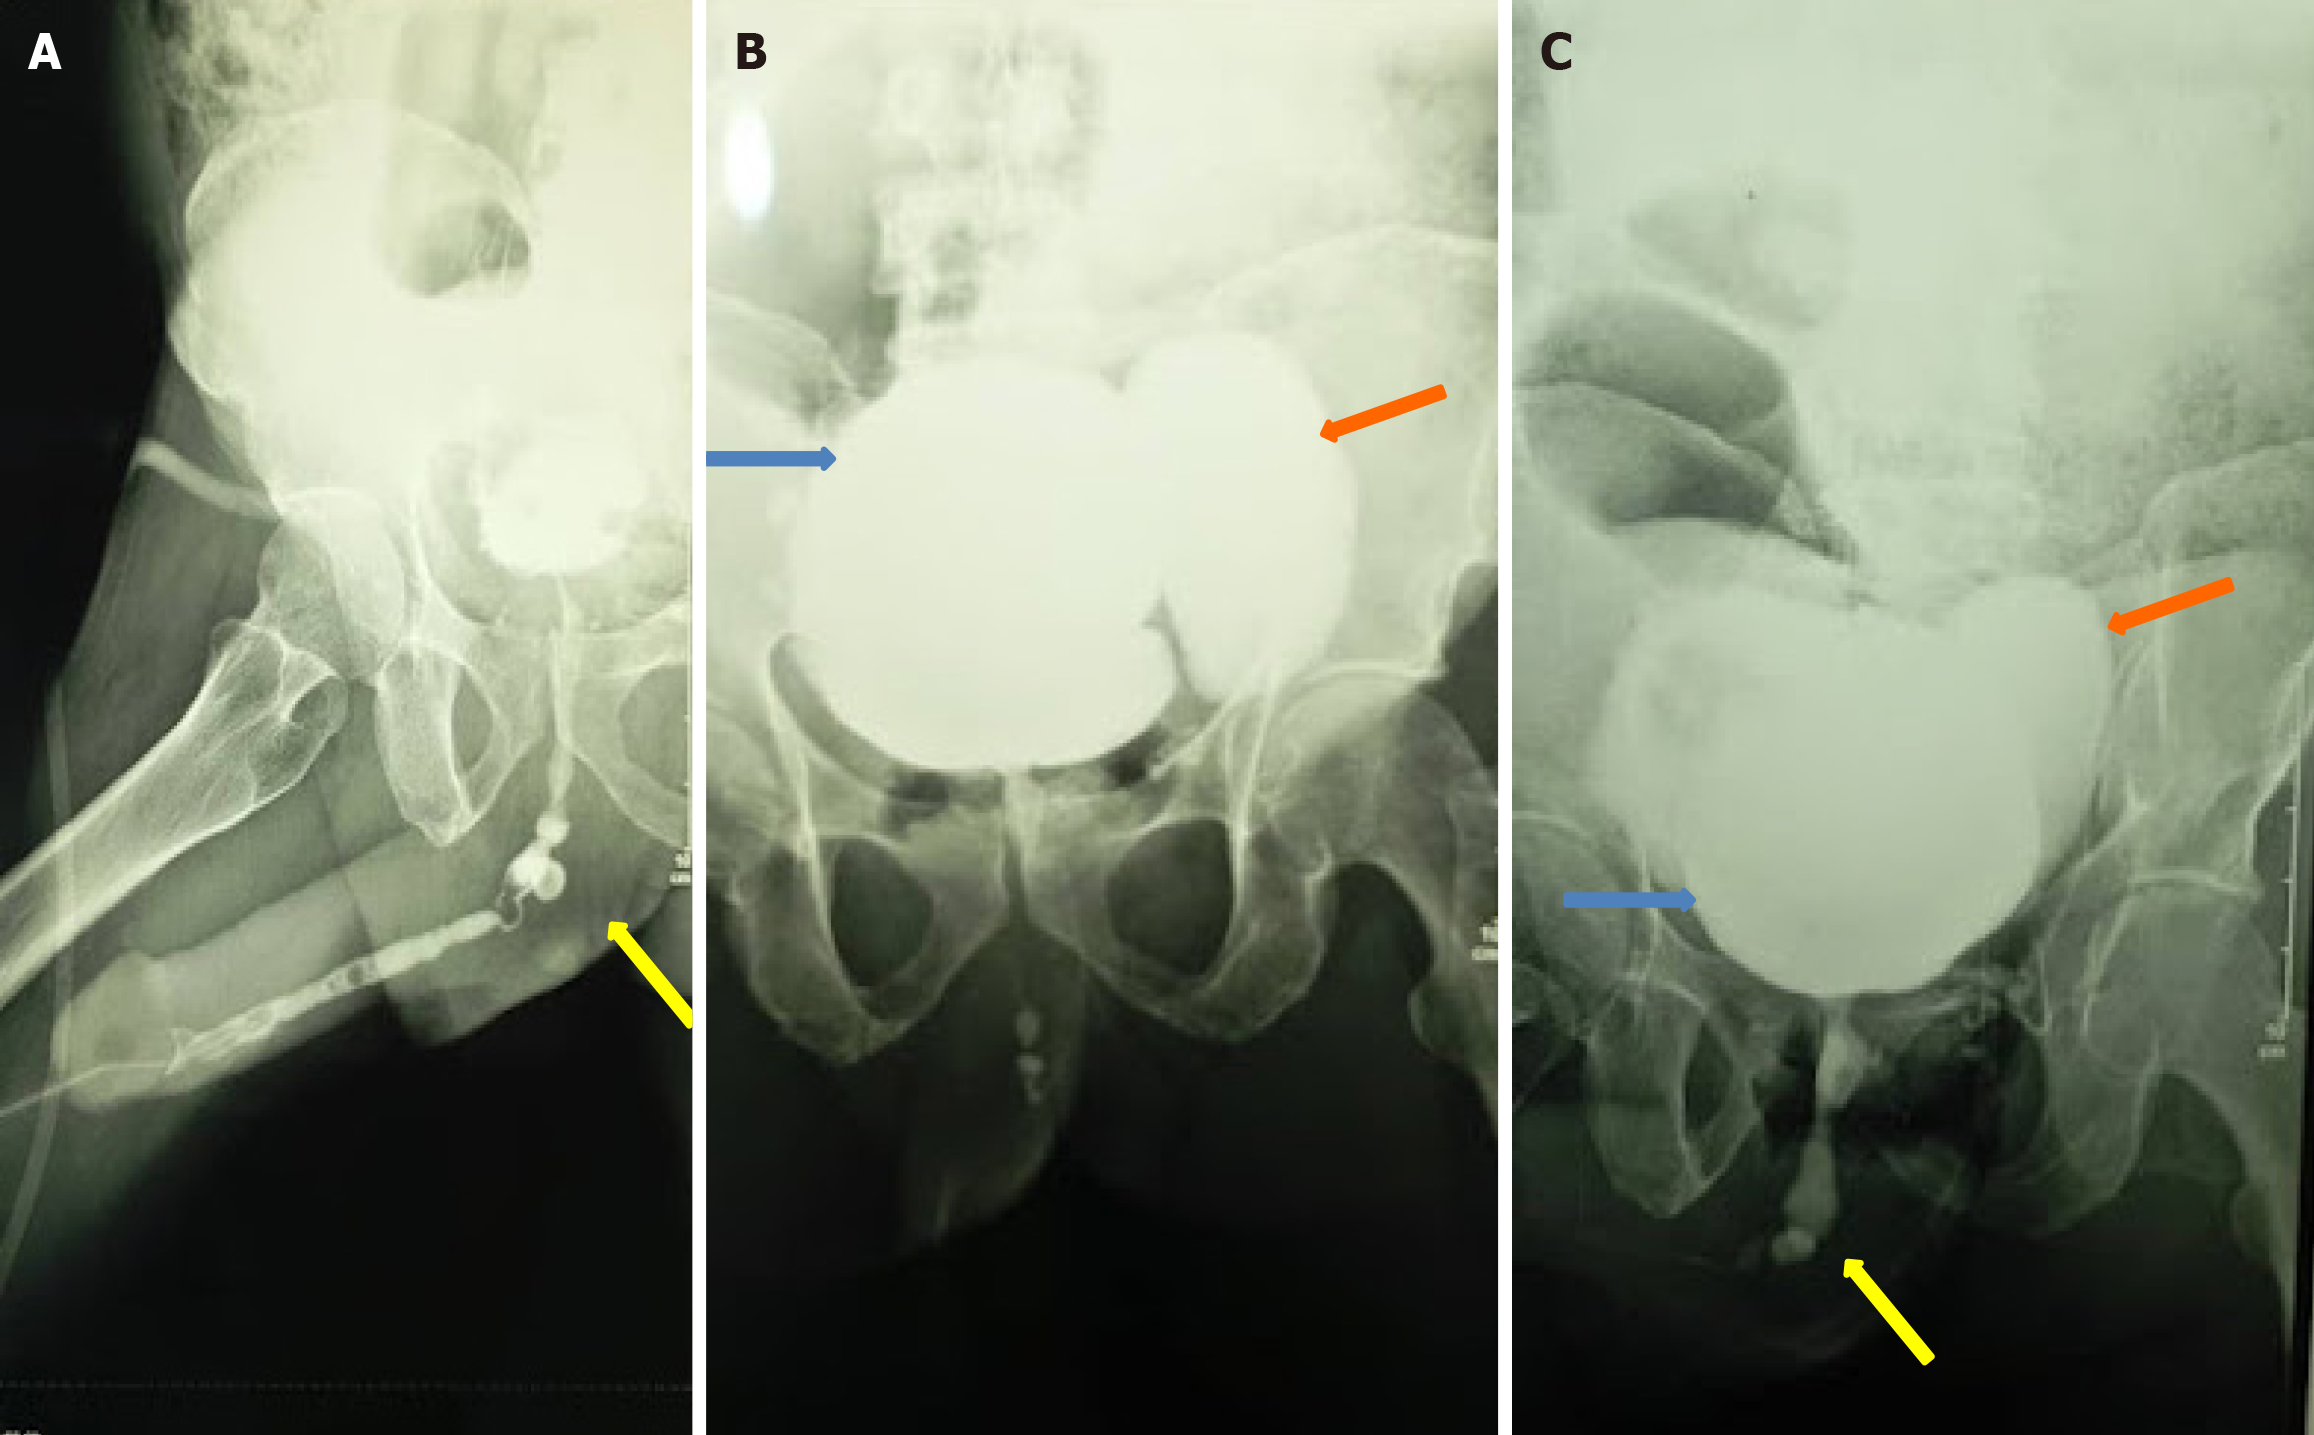

Figure 4 A combined retrograde urethrocystogram and voiding cystourethrogram demonstrating an incomplete panurethral stricture involving the bulbar and penile urethra (yellow arrow) and bladder diverticulum (orange arrow).

A: Retrograde urethrocystogram; B: Cystogram; C: Voiding cystourethrogram.